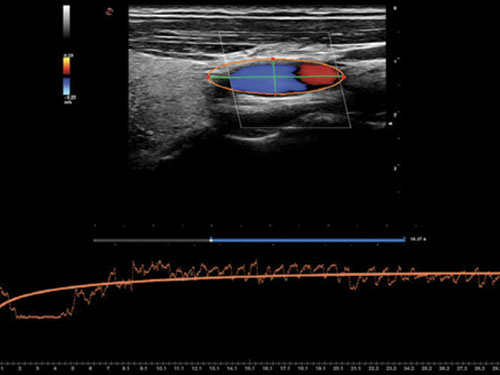

Q-Pack: Q-Pack je nový multimodální kvantifikační nástroj pro analýzu křivek Contrast Perfusion (Wi / Wo), dostupný v barvách, Power Doppler a CnTI ™.

QAS: RF datová technologie umožňuje automaticky a přesně měřit tuhost karotické stěny a automaticky vypočítat indexy PWV, CC, AI, α, β.